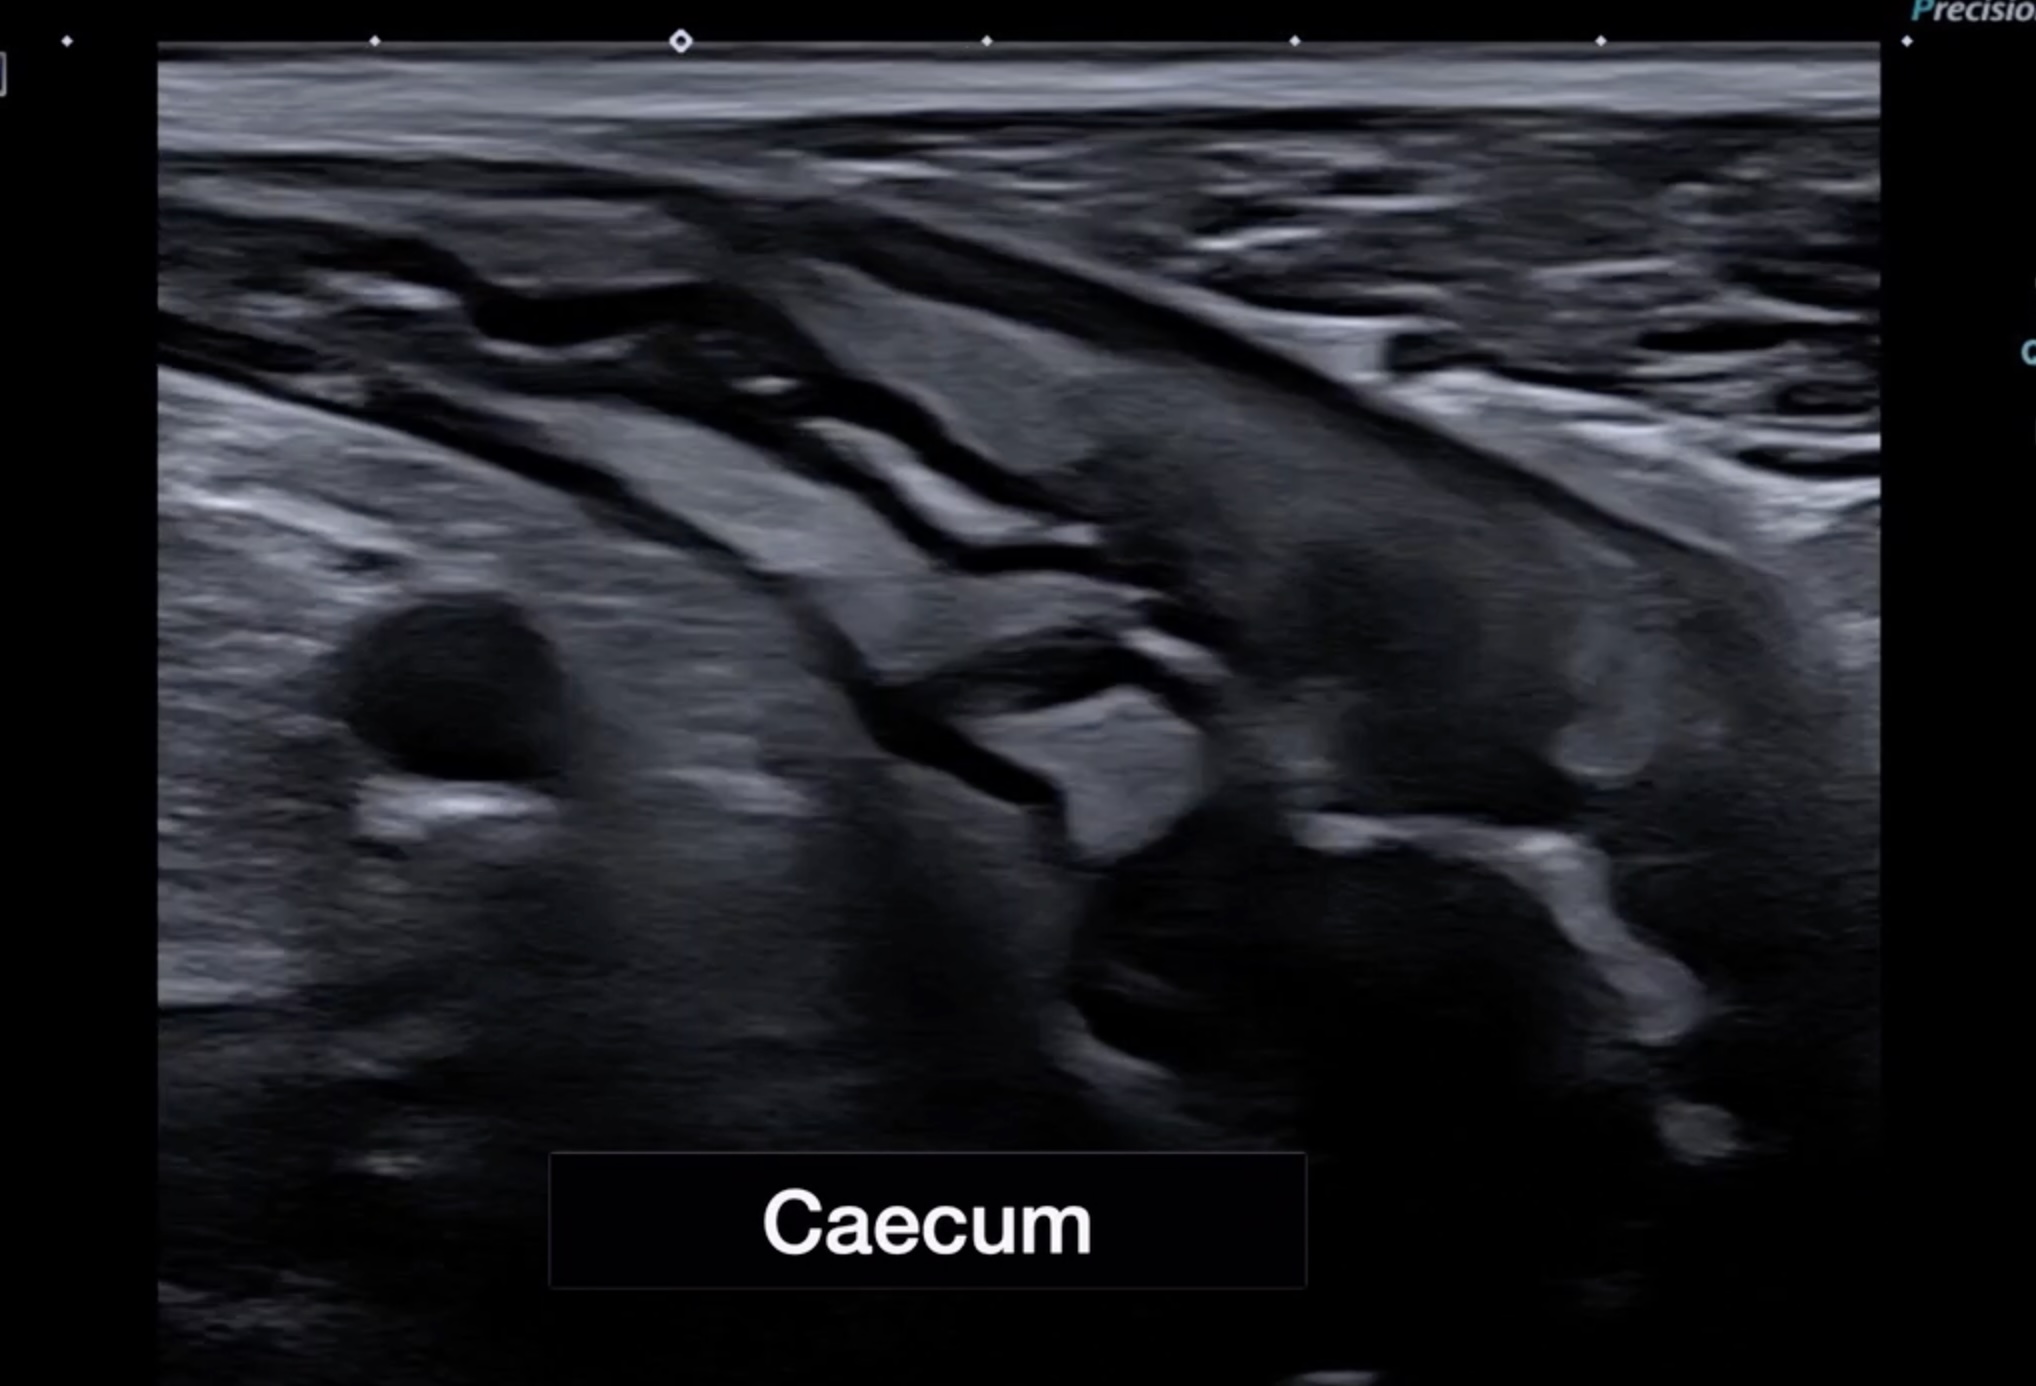

![]() Caecum , valvule et iléon atteints |

![]() Bas fond caecal |

Épaissi irrégulier et infiltration de la graisse, et Doppler, mais pas ou peu de destruction de la structure en couches.

a révélé dès la première consultation, une pancolite, asymétrique, discontinue, très inflammatoire par endroit (graisse très infiltrée, gros ganglion) évocatrice d’emblée d’une colite type maladie de Crohn prédominant au colon